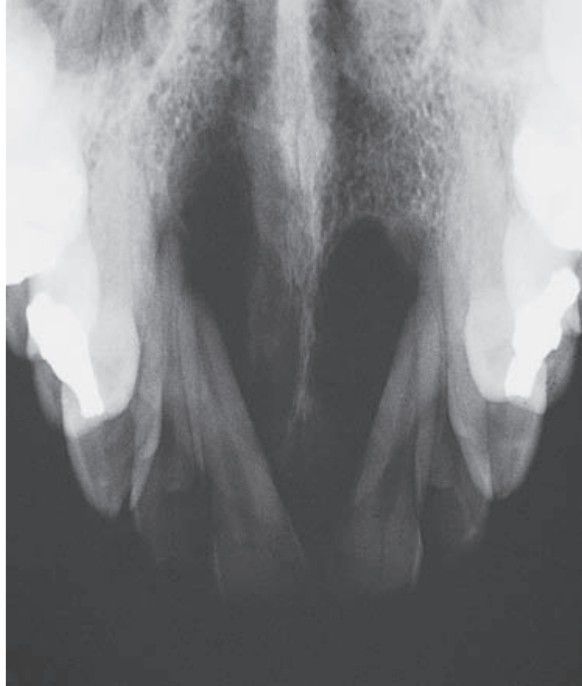

Chondrosarcoma

Chondrosarcoma of anterior maxilla